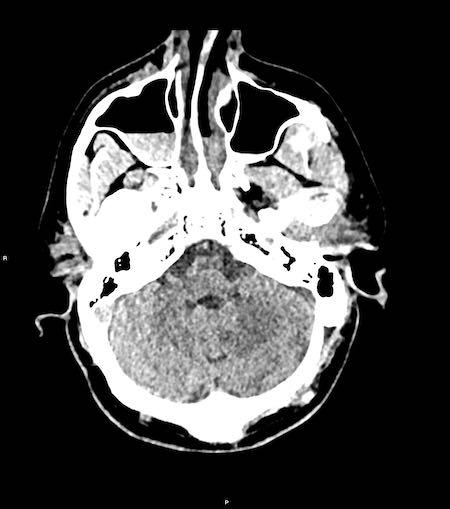

Bệnh nhân nam 46 tuổi bị chấn thương năng lượng cao khi đi xe máy.

Điểm EMV ban đầu là 2-5-3 và đồng tử hai bên giãn không phản xạ ánh sáng.

Hình ảnh CT

- Xuất huyết dạng chấm ở cả hai thùy trán.

- Gãy xương Le Fort II hai bên.